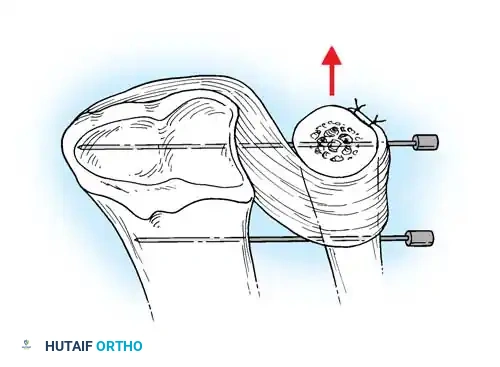

If the DRUJ remains unstable after soft tissue repair, temporary transarticular K-wire fixation may be necessary to protect the repair during the initial healing phase.

Radiographic confirmation of temporary transarticular K-wire fixation stabilizing the DRUJ following complex TFCC repair.